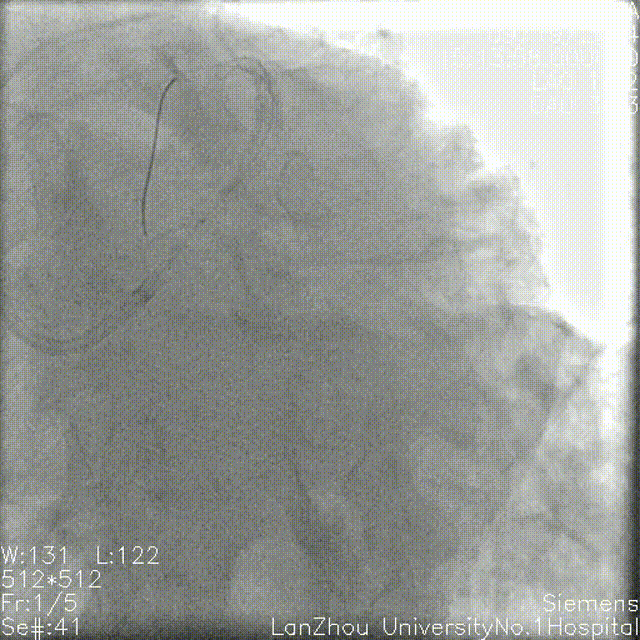

2.75*28mm支架 8atm于前降支近中段释放,复查造影狭窄解除。

复查造影提示回旋支开口仍明显狭窄,考虑使用药球后可能回弹,遂决定行支架植入,于回旋支近端-左主干行Cullotte术,2.75*18mm 10atm释放支架。

前降支Re-wire,1.5mm、2.0 mm、2.5mm球囊扩张回旋支-左主干支架网眼。

与前降支近中段原支架串联前降支近端至左主干 12atm释放3.5*32mm支架。

回旋支Re-wire, 1.5mm、2.0 mm、2.5mm球囊扩张前降支-左主干支架网眼;

2.75*15mm,3.5*12mm球囊扩张前降支-左主干,2.75mm球囊扩张回旋支;

2.75mm,3.5mm 8atm対吻扩张。